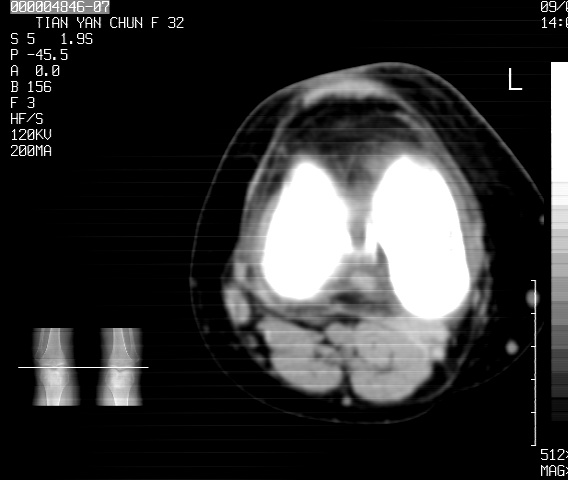

标题: CT18487:请会诊,女32岁,左膝疼痛数日 [打印本页]

标题: CT18487:请会诊,女32岁,左膝疼痛数日

关节面软骨有硬化环考虑退行性变

定位片可见髁间棘骨质增生,支持膝关节退行性变。

定位片可见髁间棘骨质增生,支持膝关节退行性变。建议mri 检查

考虑骨性关节炎